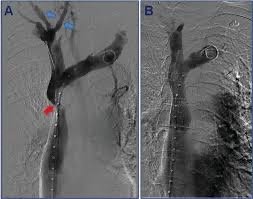

من أجل حدوث انخفاض كبير في تدفق الدم، يجب أن تتأثر كل من الشريان الأورطي البعيد والشرايين الحرقفية. يتميز متلازمة لاريش بتصلب شديد في الشريان الأورطي البعيد والشرايين الحرقفية المشتركة، مما يؤدي إلى انسداد كامل. ينتج عن ذلك أعراض مثل العرج المتقطع الثنائي في الساق والعجز الجنسي.